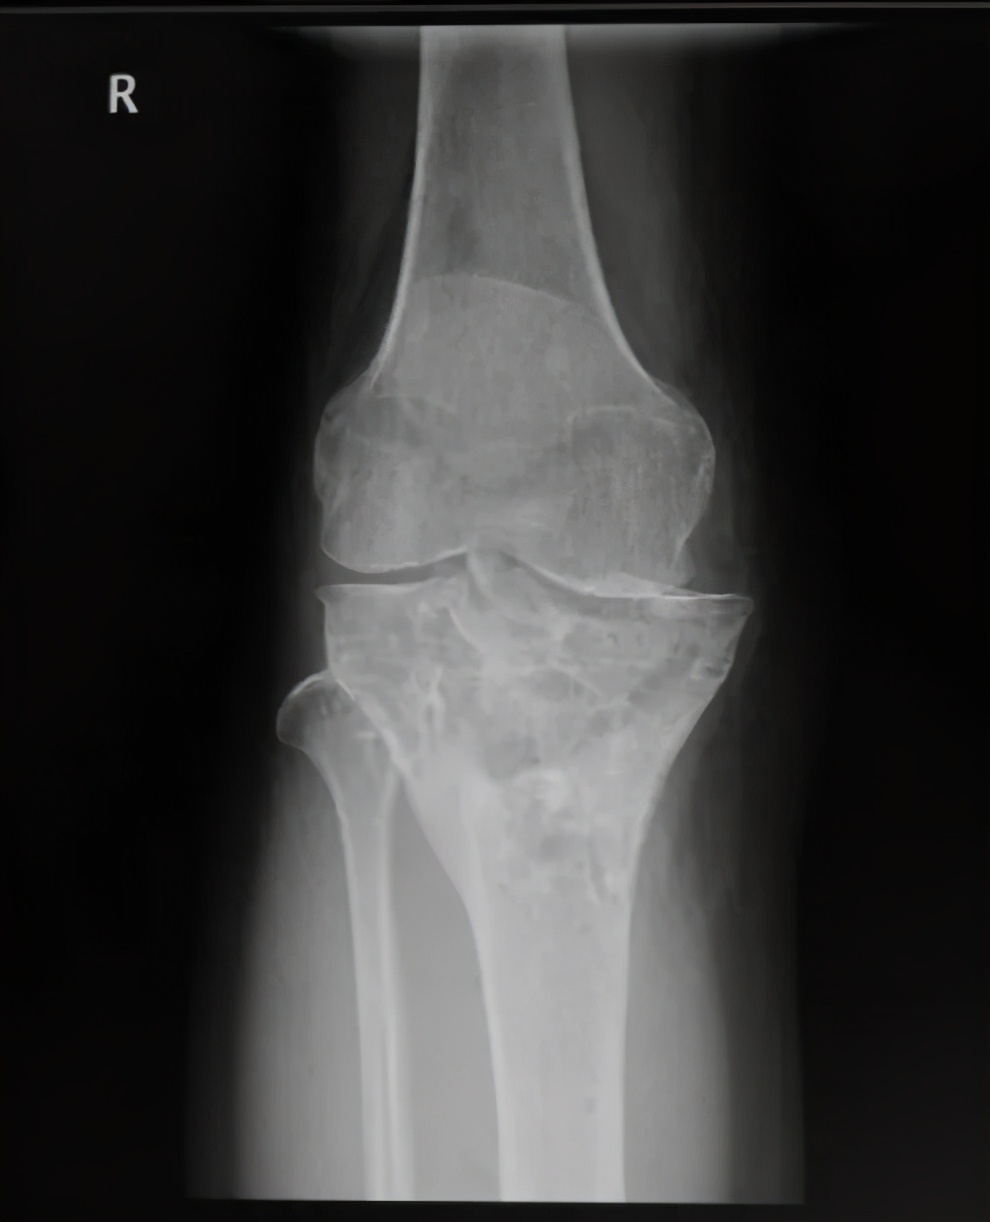

经过详细问诊以及X线检查,发现杨女士胫骨平台畸形愈合,平台大于股骨远端,膝关节对合不佳。刘万军主任决定行胫骨内侧髁截骨(TCVO),经过一系列周密的术前计划,刘主任为杨女士术前量身制作截骨模板,术后杨女士当天便可以下床活动,第二天就可以出院了,看见自己的腿由弯变直,杨女士的脸上露出了久违的笑容,对刘万军主任团队高超的医术赞不绝口。

膝内翻俗称“O型腿”,表现为双脚并拢时,双膝不能靠拢。在X线正位片上显示膝关节内外侧间隙不等宽,内侧间隙明显变窄。

正常的膝关节力线都能很好的通过膝关节中心,而在膝关节内翻的情况下,不平衡的力会对膝盖的内侧部分造成过大的压力,从而导致膝关节内侧关节软骨较早发生退变,产生膝关节骨性关节炎。